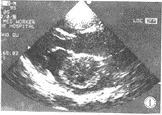

4.超聲心動圖左房粘液瘤在左心腔內見到異常的點片狀反射光團,活動於左房、左室之間,收縮期回到左房腔,舒張期達二尖瓣口進入左室,二尖瓣前葉EF斜率減低,左房增大。右房粘液瘤異常反射光團在右心腔內,收縮期在右房,舒張期隨三尖瓣向右室方向移動或通過三尖瓣口進入右室腔。右房、右室增大。

3.超聲心動圖檢查顯示瘤體隨心臟收縮和舒張活動。心血管造影顯示心腔內占位性病變,但有一定的假陽性、自有超聲心動圖,心血管造影較少套用。